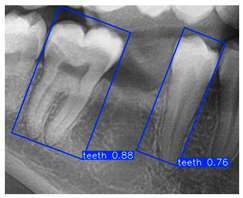

| YOLO-OBB result | ||||||

| Validation Image 1–6 | ![]() | ![]() | ![]() | ![]() | ![]() | ![]() |

| Accuracy | 84.13% 75.18% | 90.29% 76.49% | 87.38% 87.27% | 80.40% 84.48% | 70.11% 83.41% | 88.46% 76.33% |